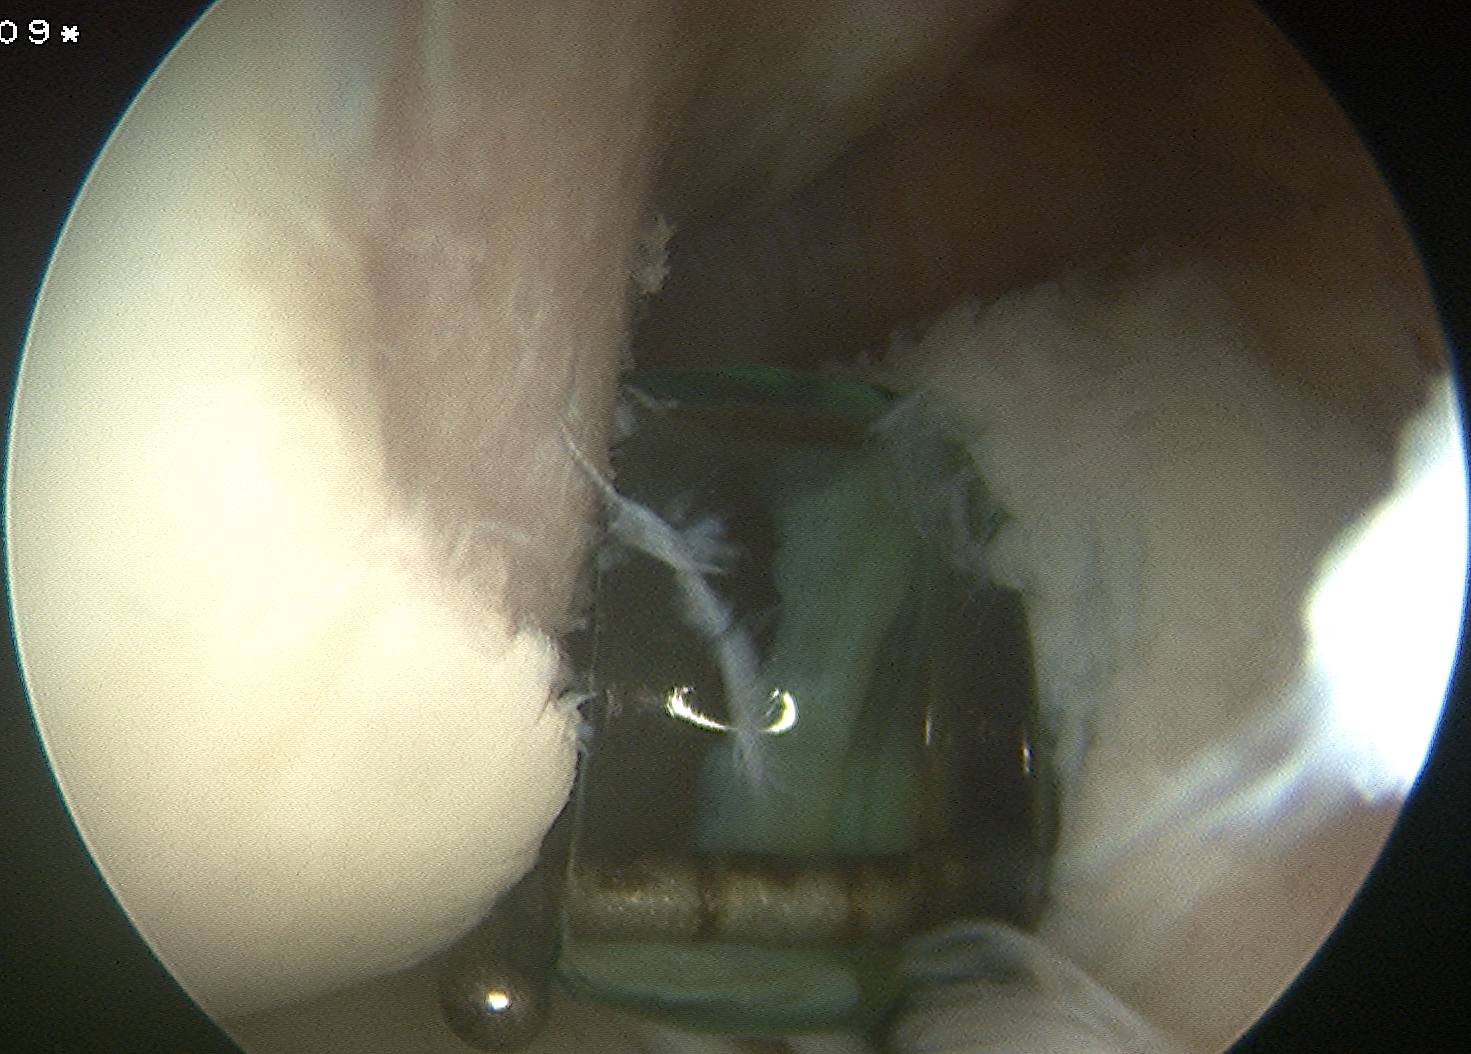

Insert anchors

Inferior anchor at 5.30 o'clock

- curved anchor guide / trans-subscapularis

- on rim of glenoid

Other anchors typically at 3 and 4 o'clock